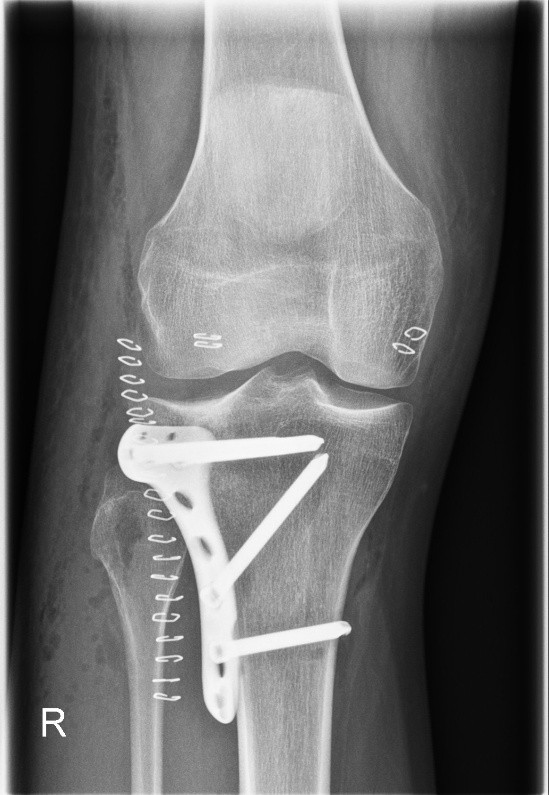

Tibiakopf Fraktur

Die arthroskopisch assistierte Frakturversorgung (insbesondere am Tibiakopf) im Rahmen von Band- bzw. Kombinationsverletzungen ist ebenfalls ein Schwerpunkt der Abteilung. Der ärztliche Direktor PD Dr. med. Schlumberger ist im DKG-Komitee „Frakturen“ vertreten.